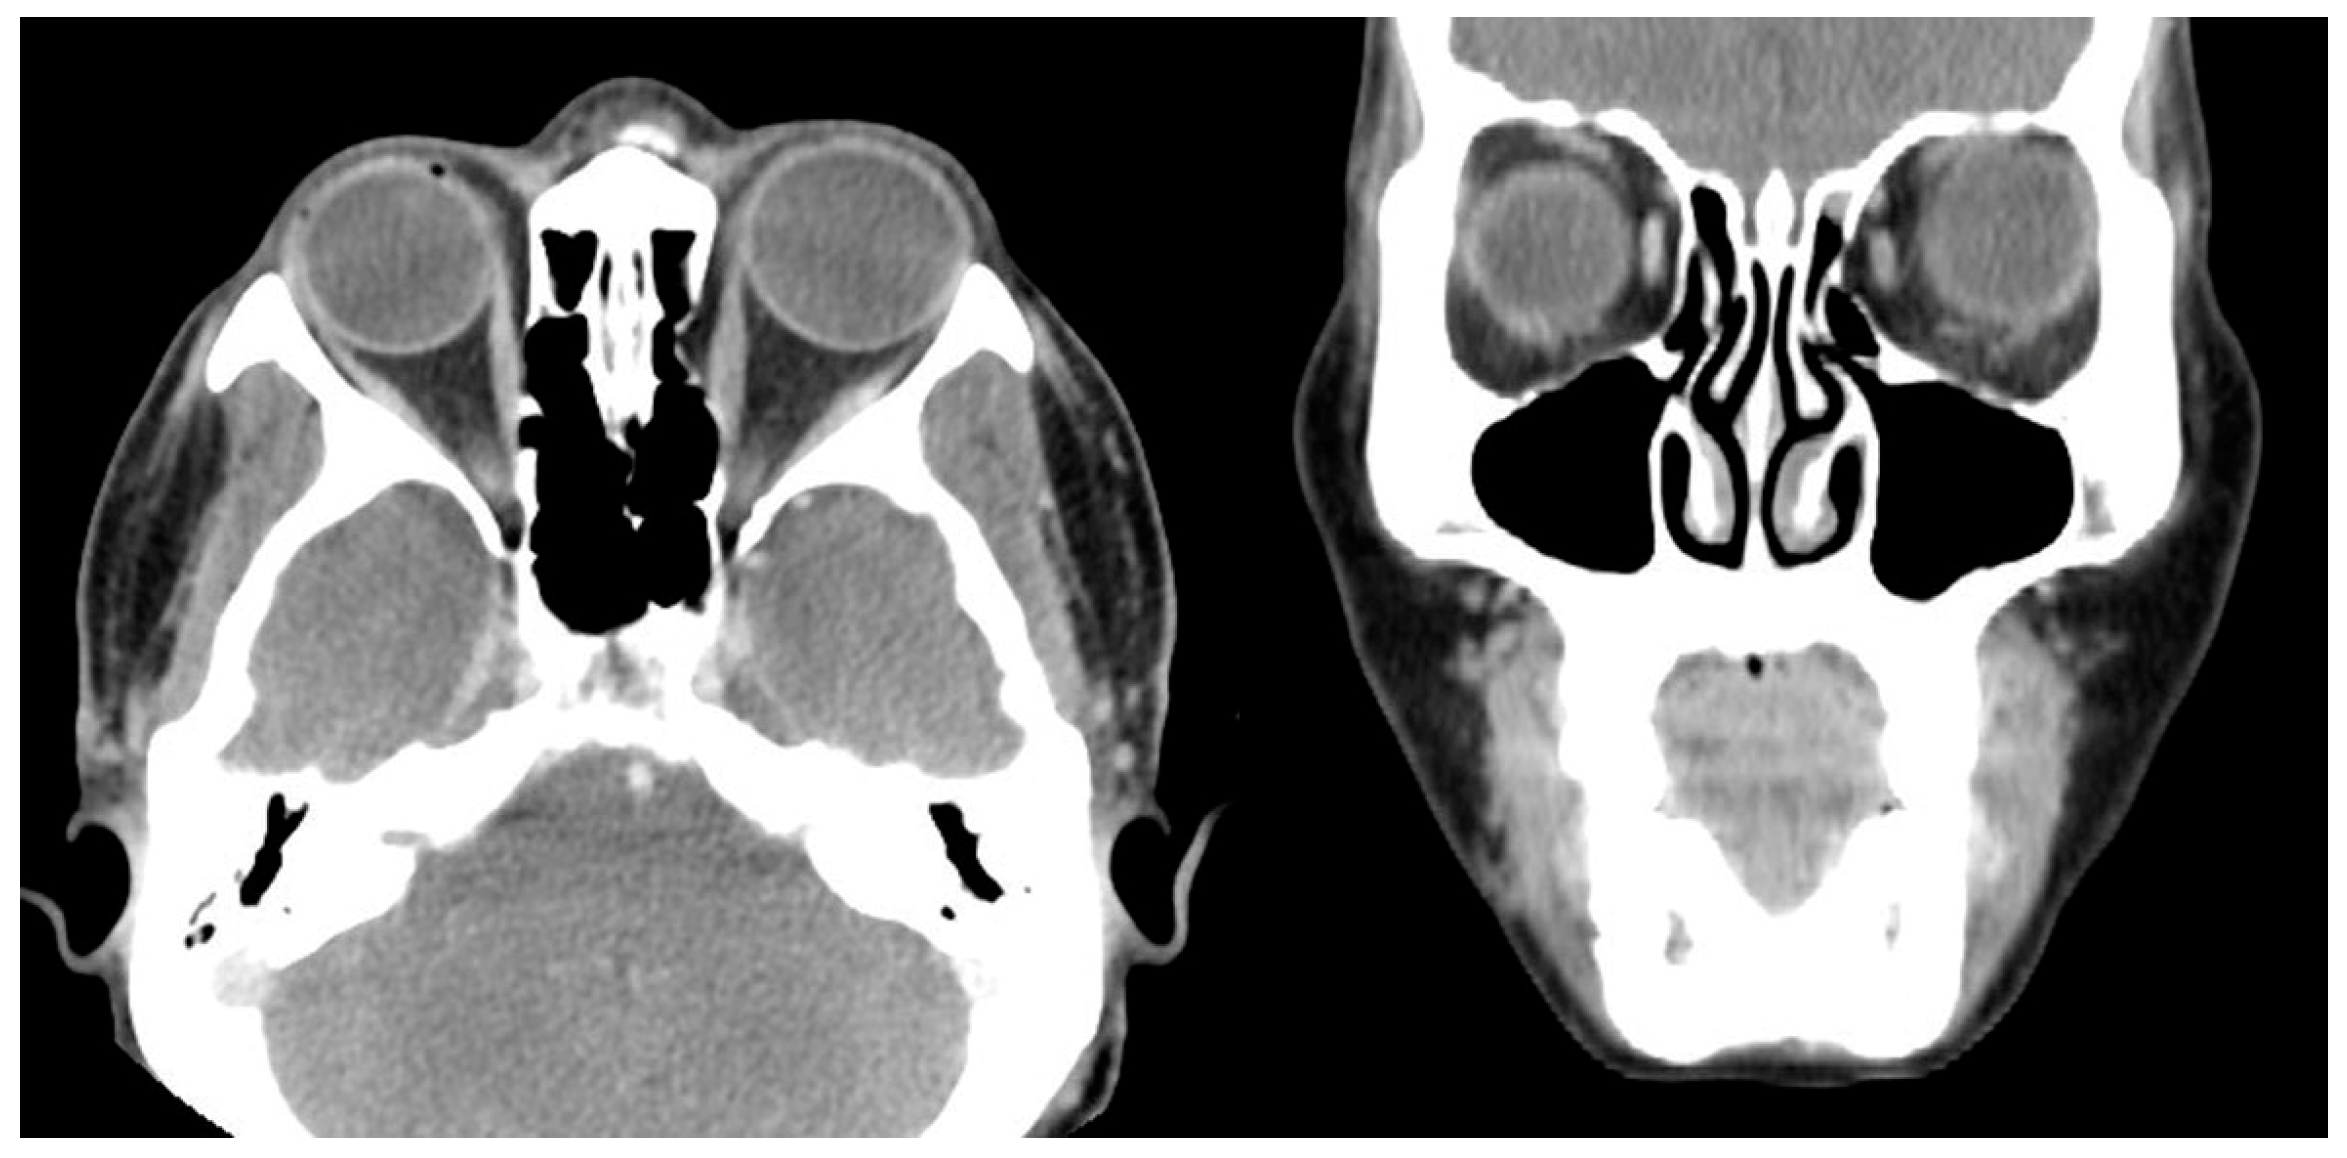

Case 2 was a 63-year-old male who presented with 100 PD ET in the right eye (Figure 1). His visual acuity was 20/200 in the right eye (SE, −0.5 D) and 20/20 in the left eye (SE, +0.5 D). Severe abduction deficit (−4) of the right eye was observed. Ten years before, the patient experienced a severe automobile accident. Optic atrophy of the right eye due to the traumatic optic neuropathy was observed during the fundus examination. Severe abduction deficit (−4) of the right eye was observed due to the sixth cranial nerve palsy that resulted from previous head trauma during the automobile accident. During strabismus surgery, severe restriction of the right MR by the forced duction test was noted, and the right MR was unintentionally disinserted during the procedure. After MR disinsertion, his esodeviation decreased from 100 PD to 30 PD and there was no restriction of the right MR. After two months, an additional right LR with a 7.0 mm resection was performed in the right eye. Two years after surgery, his esodeviation was 10 PD in the primary position of gaze without limitation in abduction or with little limited adduction (−1).

Figure 4. Postoperative CT image of Case 4. No definite abnormality is noted after left medial rectus muscle disinsertion.